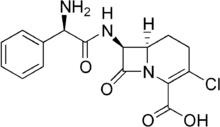

Carbacephem

Carbacephems are a class of synthetic antibiotics, based on the structure of cephalosporin, a cephem. Carbacephems are similar to cephems, but with a carbon substituted for the sulfur.[1]

Loracarbef, a carbacephem

It prevents bacterial cell division by inhibiting cell wall synthesis.